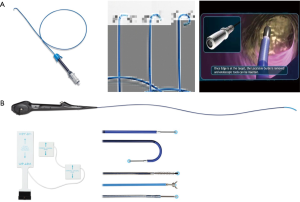

In the United States, there are two EM navigational systems available for clinical use; superDimension (Covidien, Minneapolis, MN, USA, Figure 1) and SPiNView (Veran Medical Technologies, St. Louis, MO, USA, Figure 2). Both systems are based on the same fundamental concept. A CT scan using a dedicated protocol is obtained for planning ENB targets and to overlay the magnetic field to the CT scan and the patient anatomy. The superDimension system (Covidien, Minneapolis, MN, USA) consists of several components. The main processor unit, steerable extended working channel catheter with different tip angulations ranging from 45o to 180o, a locatable guide and the EM board which generates the EM field and lies underneath the patient throughout the procedure. During the pre-procedure planning phase, the target lesion is identified using proprietary software (Figure 3, Figure 4A).

The SPiNView system (Veran Medical Technologies, St. Louis, MO, USA) uses a tracking pad that serves as a reference point, providing feedback information for the system to maintain registration despite the change in location of the target lesion due to respiratory variation. Ideally, to maximize accuracy, CT scan images are obtained during inspiration and expiration for the computer algorithm to compensate for the dynamic respiratory changes. As with the superDimension system, SpinDrive requires a pre-procedure planning phase that is performed using proprietary software loaded onto a dedicated laptop (Figure 3). The main piece of equipment is composed of a central unit with a generator that creates the EM field which projects down, over the patient. Another major difference is in the biopsy instruments. They are always-on tip trackable, eliminating the need for an extended working channel, but limiting the directionality. Because the instruments are tip-tracked, the need for fluoroscopy to ensure appropriate positioning is obviated. The biopsy forceps and brushes are 1.8 mm in outer diameter (OD) and histology and cytology needles are available in 19 and 21 gauge (G) respectively (Figure 4B).

Recently, the EM navigational technology was incorporated into the traditional TTNA technique creating a novel diagnostic tool and potentially a new paradigm in the evaluation of lung nodules. The SPiNPerc system (Veran Medical Technologies, St. Louis, MO, USA) consists of the same computer unit used with the SPiNView system for ENB, but instead of endobronchial navigation via a trackable bronchoscopic instrument, a 19 G (105 mm length) needle is use for navigation. The needle has two components, a stylet that works as a sensor allowing EM navigation to peripheral pulmonary nodules and the needle itself. Once within the target lesion the needle works as a working channel through which smaller FNA needles can be passed or core biopsies can be obtained (Figure 5) (7). Currently, this approach is only available on the Veran SPiNView System.